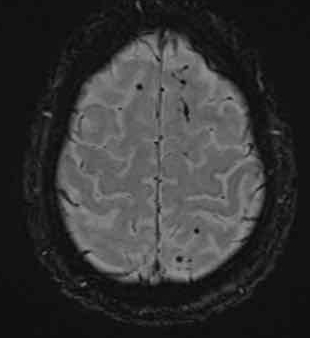

弥漫性轴索损伤(DAI)MRI表现

- 累及皮质下区、胼胝体、右侧丘脑和壳核、脑干、小脑脚和右侧小脑半球。

- 轻度全球萎缩。

MRI可准确诊断DAI,包括T2*GRE或SWI。

DAI在颅脑损伤患者MRI上的存在,更有可能导致不良的功能结局。

MRI可分为三个阶段:

- 脑叶白质可见病变

- 胼胝体损伤

- 脑干损伤

随着MRI分级的进行,不良预后也增加。

胼胝体病变尤其与不利的功能结局有关。